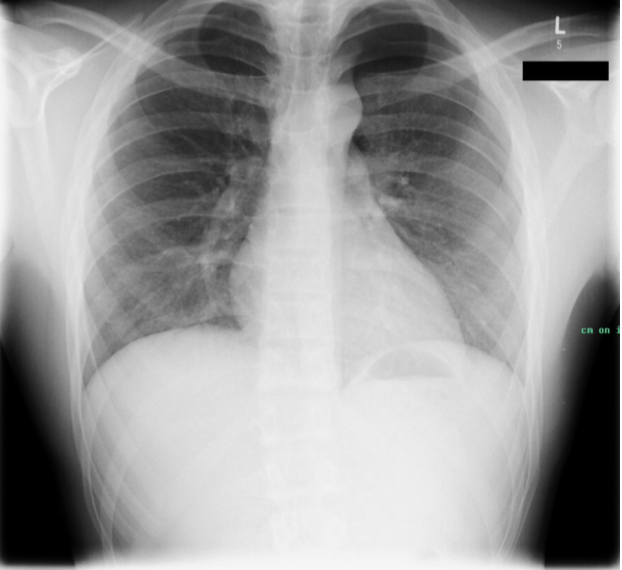

What are findings of a pneumothorax on a CXR?

CXR